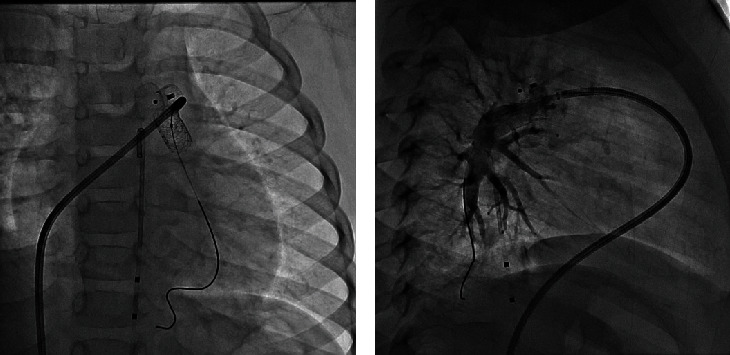

Percutaneous device occlusion is currently the standard of care for most cases of patent ductus arteriosus (PDA). Albeit infrequent, device-related left pulmonary artery (LPA) stenosis is a known complication of this procedure, occasionally requiring stent placement to relieve the obstruction. We present a series of four patients who required left pulmonary stenting after ductus arteriosus device closure. A review of the current evidence is presented.

Abstract Image